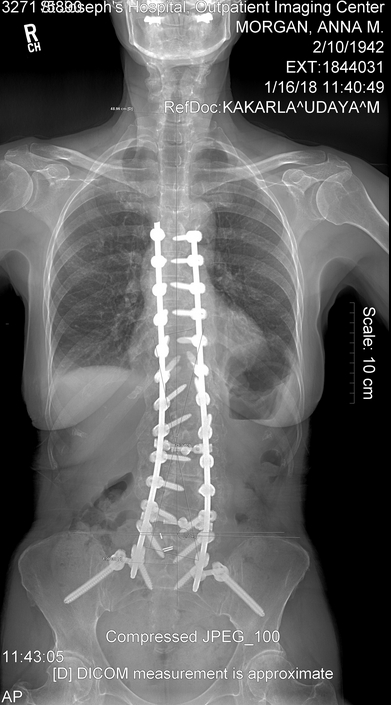

I go January 16 to have my year X-ray and be checked. If everything is healing correctly and the hardware is holding, I will accept this as my new normal.

My year is up and I have had my 1 year x-rays and Surgeon appointment. Everything looks to be holding. I guess you would say that I no longer have scoliosis. I do still have that cardboard feeling in the muscles of my back. I mentioned to Dr. Kakarla that when I try to lift a gallon of milk the back goes into spasms and gets tighter. He decided that I needed another 30 sessions at physical therapy to make my upper body and legs stronger.

I still am doing the 4 mile hike. So with 3 times a week at PT and the hike my days are busy. Hope we can get started with our summer by Easter. Here are two views of my spine at my one year checkup.